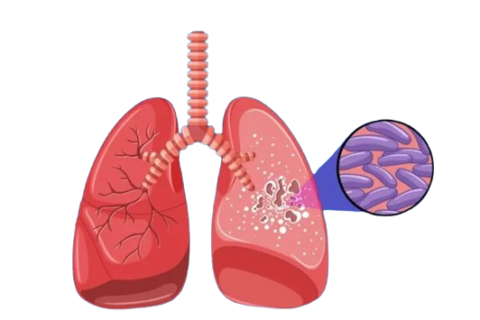

The International Diabetes Federation (IDF) officially recognized a fifth form of diabetes in 2025, after decades of controversy. It’s now urging other health authorities, like the World Health Organization (WHO), to follow suit. Type 5 diabetes is…